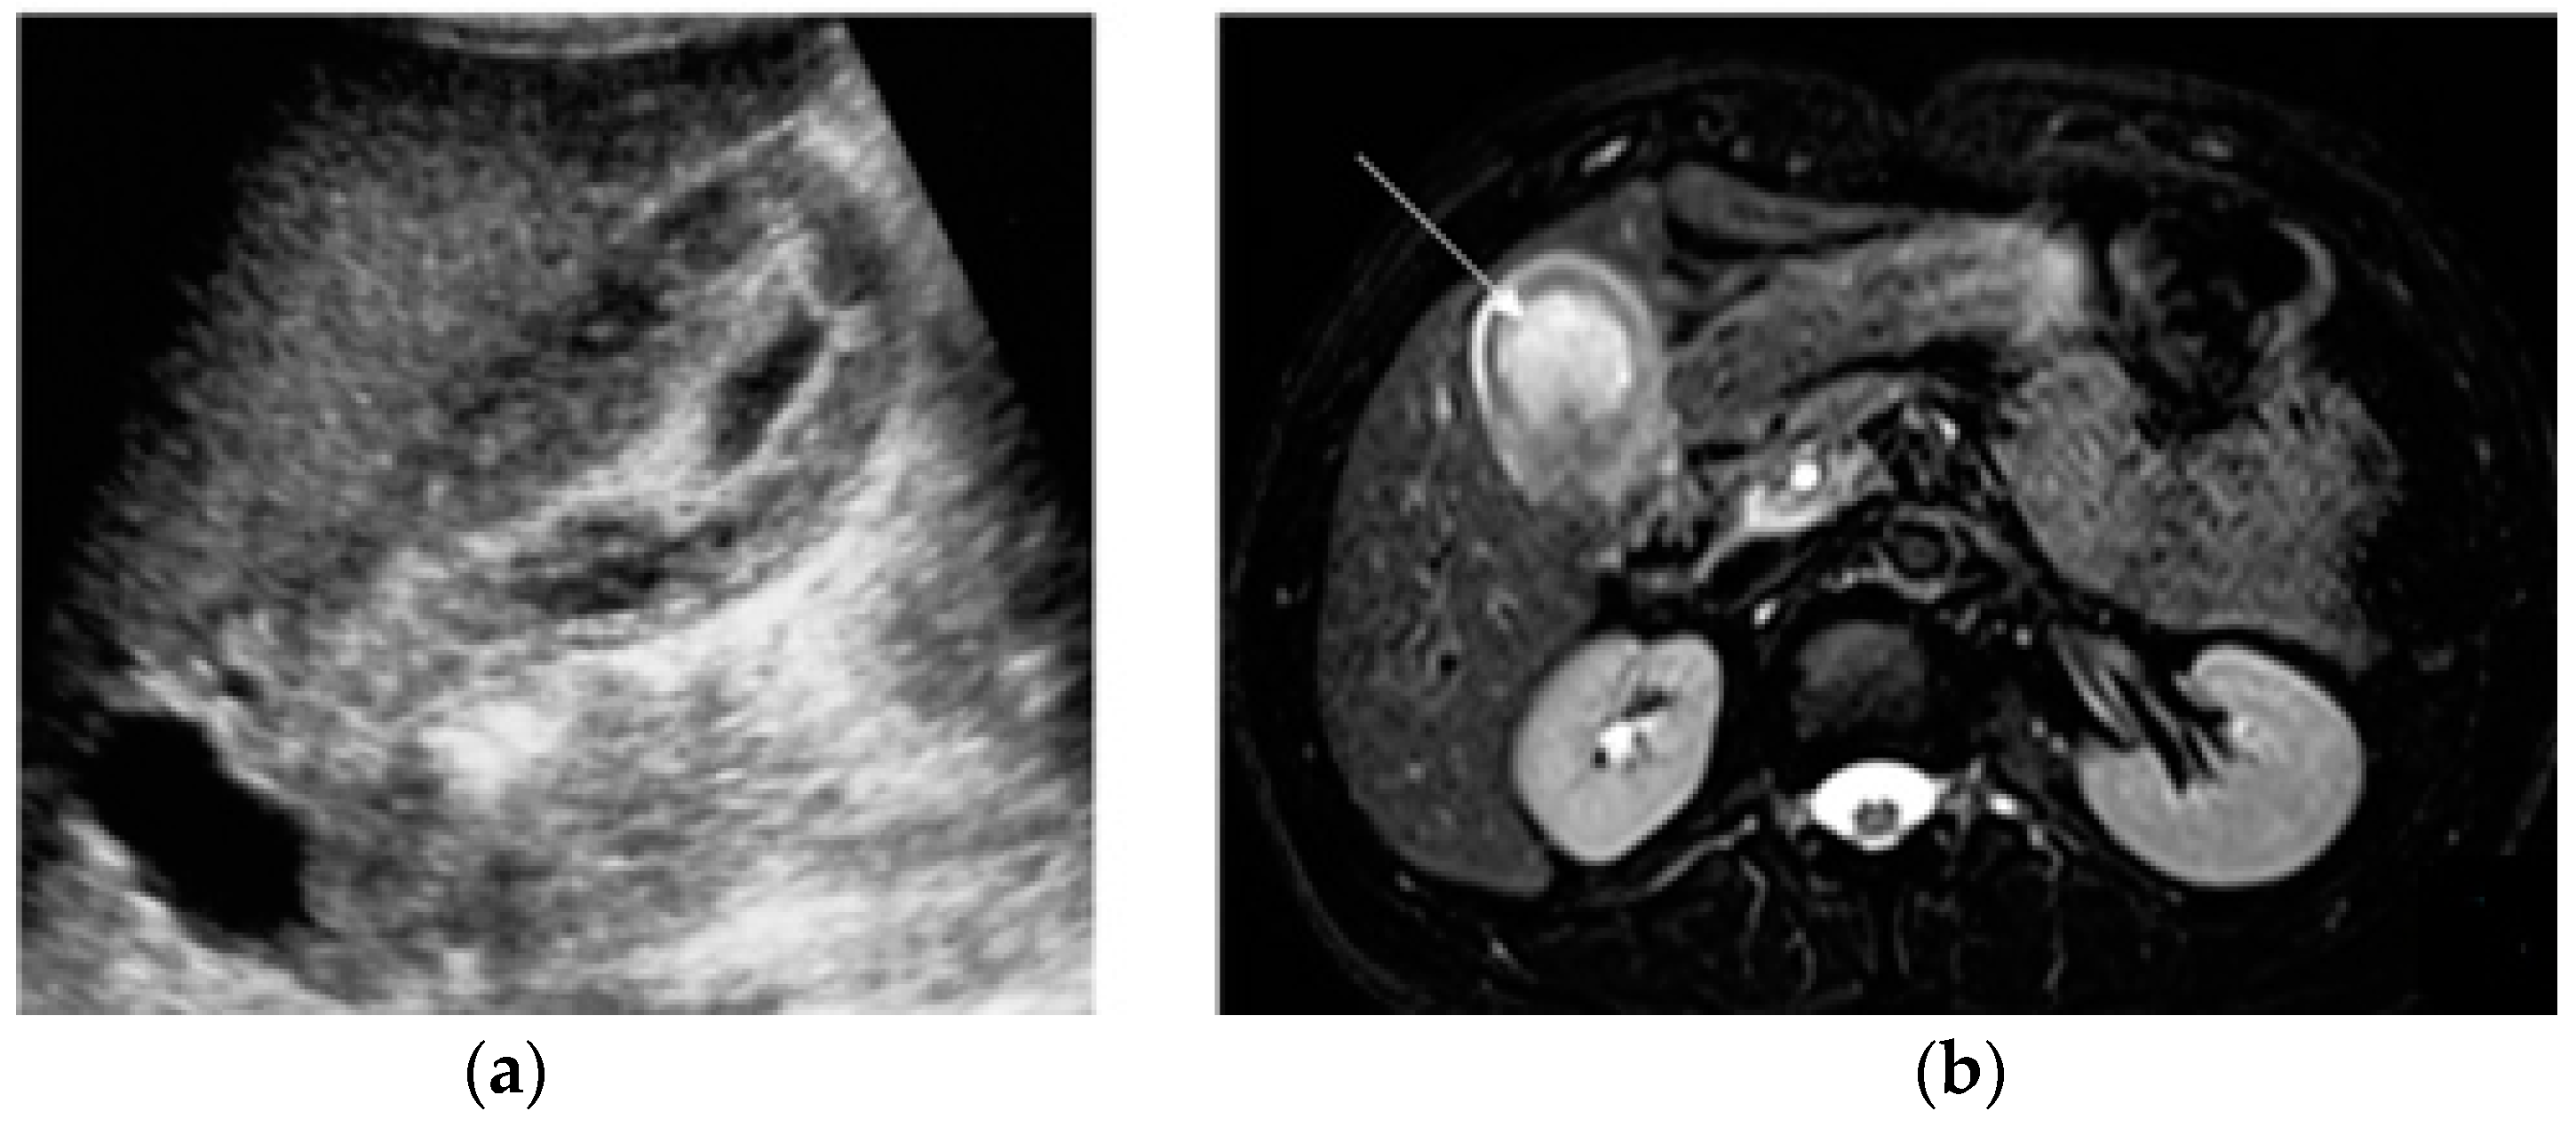

The impaired egress of urine (urinary stasis), due to stones, increases the risk of complications, such as acute pyelonephritis, reported in 1% of pregnancies [80]; in these cases, MRI could be a useful adjunct to clinical diagnosis. The DWI sequence in particular has been found to have increased sensitivity when compared to non-contrast CT (95% and 67%, respectively). The kidney appears enlarged and edematous with areas of lower signal intensity on T2-weighted images and restricted diffusion on DWI (Figure 7).

Figure 7.

Acute pyelonefritis in a 28-year-old woman at 23 weeks of gestation presenting with right-sided abdominal pain and fever. Axial T2WI fat-sat image (a) shows an enlarged right kidney with a dilated pelvis. Axial DWI b-800 (b) clearly depicts wedge-shaped areas of high signal intensity in the right kidney, consistent with the foci of nephritis.

In patients who develop renal abscesses, T2-weighted and DW images respectively show a focal, more hyperintense signal and restricted diffusion, compared to the rest of the parenchyma involved in nephritis [3,54] (Figure 8).

Figure 8.

A 21-year-old woman at 20 weeks of gestation was admitted to the hospital with a diagnosis of pyelonephritis and a temperature of 39.4 °C. Coronal T2-weighted HASTE (a) and axial T2-weighted fat-sat images (b) show a large right-sided and thick-walled fluid collection (arrows), consistent with renal abscess, displacing the kidney.